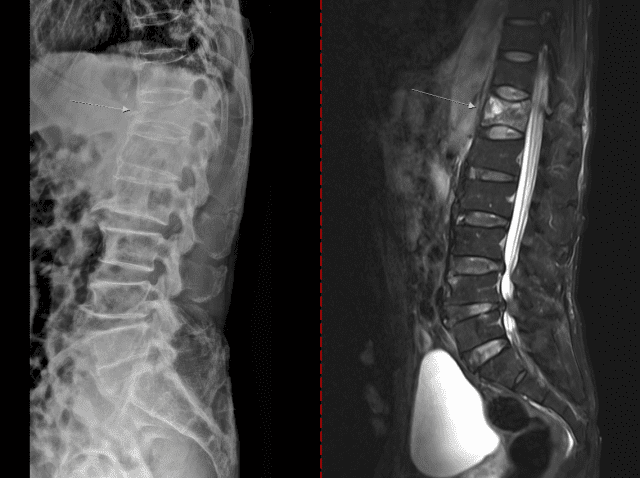

치료 없이 방치하면 뼈는 점점 약해지고 척추와 손목, 대퇴골 골절 등이 발생할 수 있다. 대퇴골 골절은 고령 환자에서 수술 후 합병증, 장기 입원, 사망률 증가와 직결되는 중증질환이다. 척추 압박골절의 경우 자세 변화, 만성 통증, 보행 장애를 유발해 ▲활동량 감소 ▲근력 저하 ▲추가 골절의 악순환으로 이어진다.